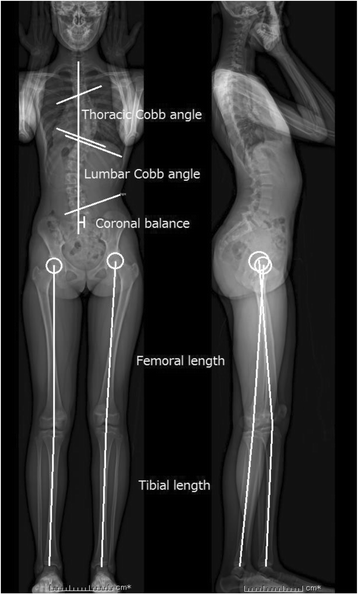

Fig. 3

Measurements obtained using whole-body EOS radiography in the upright position. Thoracic Cobb angle, lumbar Cobb angle, and coronal balance were assessed in the coronal plane obtained from whole-body EOS radiography. Structural leg length discrepancy was defined as the difference between the sums of the bilateral femoral and tibial lengths obtained from three-dimensional distance using the EOS system